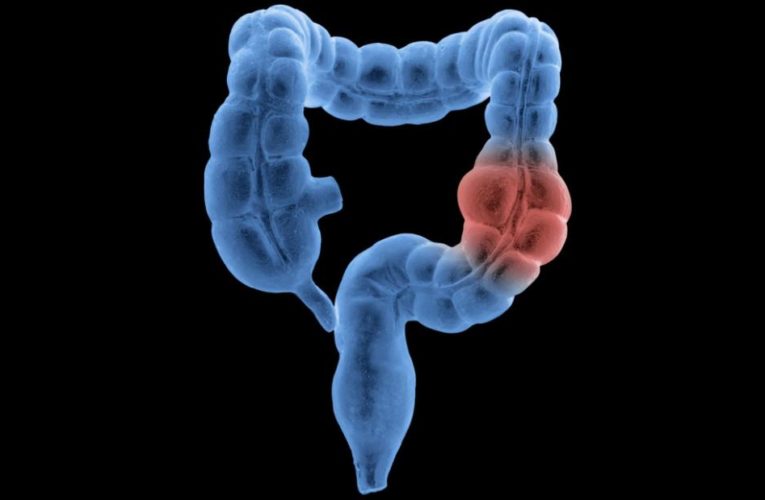

Half of new colon and rectal cancer diagnoses are now in people age 66 and younger, report finds

The report, published Thursday in CA: A Cancer Journal for Clinicians, found that the median age when people are diagnosed with colorectal cancer was 72 in 1989, stayed that way … Read More